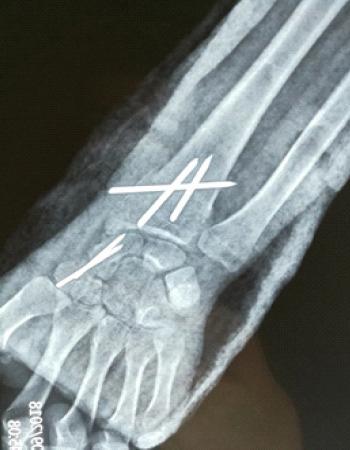

A 22-year-old female was admitted to the emergency department following a fall while exercising which resulted in severe pain in both wrists without any neurovascular deficit. X-ray imaging showed bilateral combined fractures of the scaphoid and distal radius. To fix the fractures, the patient underwent closed reduction and internal fixation with Kirschner wires along with immobilization for 3 months. The radius and scaphoid fractures were united within approximately 6 and 10 weeks, respectively.

一名22岁女性在锻炼时摔倒后被送往急诊科,导致双腕剧痛,无任何神经血管损伤。X线成像显示双侧舟状骨骨折合并桡骨远端骨折。为固定骨折,患者接受了克氏针闭合复位内固定,并固定3个月。桡骨和舟状骨骨折分别在大约6周和10周内愈合。